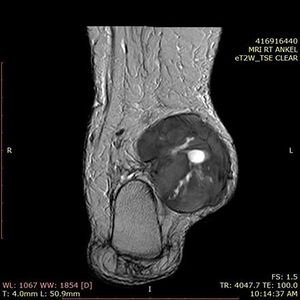

Case History: 60-year-old patient presented with complaint of bilateral lower limb swelling.